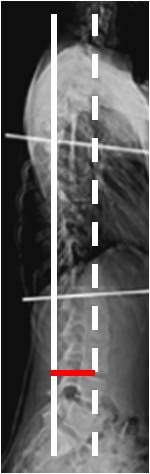

La escoliosis se define como una curvatura espinal lateral en el plano coronal, con un ángulo de Cobb mayor de 10º. Un ángulo menor de 10º, asintomático y que no progresa, se conoce como asimetría espinal o curvatura y no escoliosis. (3, 5, 25, 26). (Fig 10).

Fig 10. Asimetría espinal.

A y B: Rx AP. Desviación en los ejes de la columna. En A dorsal derecha y en B lumbar izquierda, pero de poca magnitud por asimetría.